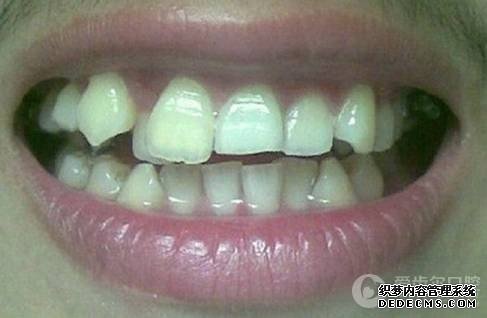

患者自述:眼看快到而立之年,身边好友都已成家立业,可我依然孤身一人,难免有些落寞。可是因为牙齿不齐,让我总是缺乏自信,性格也变得内向腼腆,几次相亲都被心仪的女孩拒绝。为了不被自卑心吞噬,我决定通过牙齿正畸改变自己,给自己一次幸福的机会。

矫正前照片